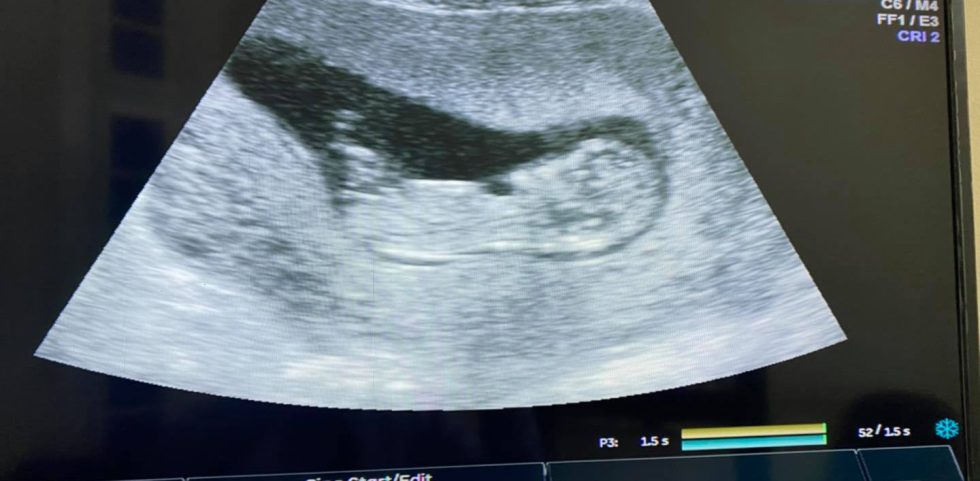

حمل على غير توقع

بعد فترة طويلة من تأخر الحمل

و بعض المشاكل الصحية الاخرى

و التصاقات شديدة بالحوض

و بعد ولادة جميلة لبنوتة زي القمر بعد حقن مجهري موفق

وأثناء الرضاعة

و بدون نزول دورة

شويةأاعراض كده غريبة

جينا نكشف و نطمن

بنعمل سونار

لقينا المنظر المبدع ده

تبارك الخالق العظيم

وربنا يكمل حملها علي خير بإذن الله